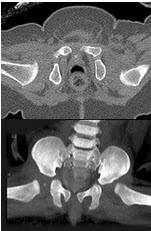

男,根据其正常骨盆影像图像,判断其最可能的年龄()

A.68岁左右

B.58岁左右

C.18岁左右

D.48岁左右

E.28岁左右